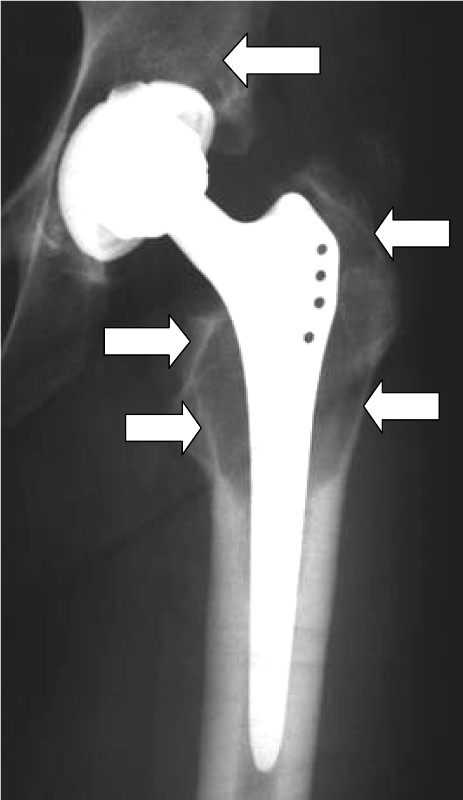

Although statistically only a small proportion of patients develop such hypersensitivity (the figures are less than 1% or between 1 and 4%, depending on the author), we attach great importance to the diagnosis and treatment of hypersensitivity reactions to prostheses in our hospital. If there is a proven allergy to prosthesis components, patients can be fitted with special prostheses made of titanium (hip) or implant coatings (knee). All-ceramic prostheses are currently still undergoing clinical trials. Before considering an implant allergy, however, other causes of the complaints, such as infections, mechanical problems or malpositioning, should be ruled out.

Skin tests (epicutaneous tests) do not show a clear correlation to the reaction of a joint to the implant, so that even skin testing for a metal or cement allergy cannot give a 100% indication. Therefore, in case of doubt, it is necessary to perform a tissue biopsy from the affected joint to provide the appropriate level of certainty. In the case of an allergy, lymphocyte infiltrates are frequently found in these tissues.

Beschichtete KnietotalendoprotheseDiffuse Lymphozyteninfiltration in der GelenkkapselOsteolyse um einen Prothesenschaft (Pfeile)